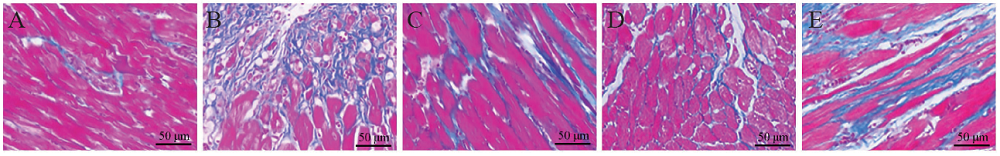

二、HE染色观察大鼠心肌组织形态变化

HE染色结果显示,假手术组心肌组织结构正常、完整,心肌细胞分布均匀、有序,轮廓清晰可见,胞核与胞质边缘分明,血管管腔完整;与假手术组比较,模型组心肌组织则呈现着色较浅、组织排列紊乱、细胞轮廓不清晰和细胞破碎现象,伴有炎症细胞浸润;与模型组比较,柚皮素高剂量组心肌组织排列较为整齐,着色均匀,有少量炎症细胞浸润,血管管腔完整度较好,但阿司匹林组和柚皮素低剂量组心肌组织仍存在一定程度排列紊乱和心肌细胞核质不清晰的现象,整体着色较浅;见图1

图1 各组大鼠心肌组织形态变化(HE染色,×400)

A:假手术组;B:模型组;C:阿司匹林组;D:柚皮素高剂量组;E:柚皮素低剂量组

LVEF、LVFS、LVESD和LVEDD是评价心脏功能的常用指标。本研究结果显示,与假手术组比较,模型组LVEF和LVFS均降低,LVESD和LVEDD均增加,与模型组比较,阿司匹林组、柚皮素高剂量组和柚皮素低剂量组LVEF和LVFS增加,LVESD和LVEDD降低,表明心肌梗死后大鼠的心功能降低,出现明显的心室扩张和重构,阿司匹林、高剂量和低剂量的柚皮素处理后可改善大鼠的心脏功能,减轻心肌梗死后出现的失代偿性心室扩张。心肌细胞属于终末细胞,当发生心肌梗死时会造成不可逆转的组织缺血坏死,从而诱发机体产生自我保护反应,包括早期无菌性炎症反应和修复期成纤维细胞增殖、瘢痕及血管形成等活动,然而,持续的炎症损伤和过度的修复反而加剧细胞死亡和心肌收缩功能障碍,不利于心功能的改善[15,16]。本研究采用HE染色和Masson染色观察各组大鼠心肌梗死后心肌组织病理生理学改变,结果显示假手术组心肌组织结构正常、完整,心肌细胞分布均匀、有序,轮廓清晰可见,胞核与胞质边缘分明,血管管腔完整,仅部分血管周围有少量呈蓝色的胶原组织;与假手术组比较,模型组大鼠心肌组织排列紊乱、细胞轮廓不清晰,呈紫红色的心肌组织明显减少,存在大量呈蓝色的胶原纤维;与模型组比较,柚皮素高剂量组心肌组织排列较为整齐,血管管腔完整度较好,组织形态优于阿司匹林组和柚皮素低剂量组,Masson染色显示柚皮素高剂量组和阿司匹林组蓝色胶原纤维大量减少,但柚皮素低剂量组仍存在较多的蓝色胶原纤维组织,组织分布相对较紊乱,表明一定剂量的柚皮素能够抑制心肌梗死导致的组织损伤,减轻心肌组织胶原纤维的沉积。